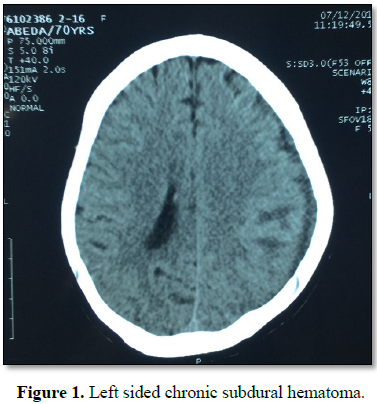

T This lady of 70 years was admitted

under our care following a prolonged period of care outside our facility. She

was previously admitted with a history of slipping and hitting her head 2 years

back and was admitted with signs of moderate head injury. Following evaluation,

she was diagnosed as a case of left sided subdural hematoma. The size of the

hematoma and the progression of the patient demanded a conservative approach in

this patient. Later she was discharged in good health. But 6 months into the

incident she developed convulsions starting on one side of her body and lasted

for 2-3 min, this followed with right sided hemiparesis which progressed

slowly. The patient was admitted again with an increase in the size of the

subdural hematoma (Figure 1).